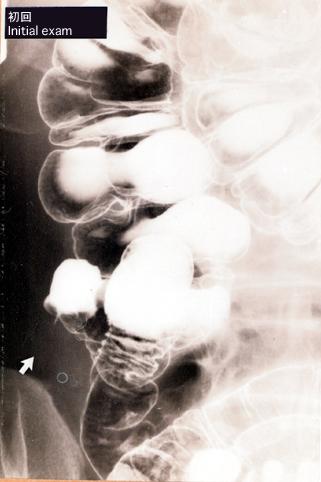

A case of appendicitis in which the initial x-ray examinations showed tumor like finding such as abrupt Interruption.

Inflammatory or ulcerative disease / lesions/Others

Large intestine(Colon)/Appendix

X-ray